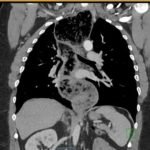

The chest X-ray demonstrated a markedly widened mediastinum (red brackets), raising concern for thoracic aortic aneurysm/aortic dissection, which prompted labs and contrast-enhanced computed tomography (CT) of the chest. The CT revealed a dilated proximal esophagus that narrowed distally (yellow tracing and red arrow), with particulate material, mass-effect on the trachea (purple outline), and bilateral patchy opacities suggesting aspiration. Barium esophagram showed a drastically dilated esophagus filled with contrast (yellow arrow), terminating into the classic “bird’s beak sign” (red arrow) at the lower esophageal sphincter (LES). Esophageal manometry later confirmed achalasia, proving that widened mediastina can have unexpected etiologies.